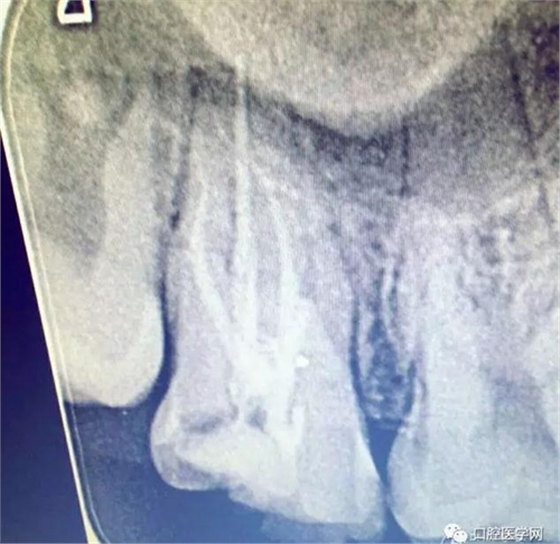

查體:27遠(yuǎn)中大面積齲壞近髓腔,探(+),冷熱(++),扣(+),無(wú)松動(dòng),口內(nèi)X片可見(jiàn)27遠(yuǎn)中齲壞達(dá)髓腔,牙周情況良好。

大錐度冷牙膠充填根管治療后